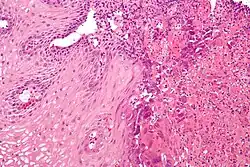

![]() | |

An esophageal ulcer visualized by esophagoscopy: the reddened area at 10 o'clock on the surface of the mucosa. | |